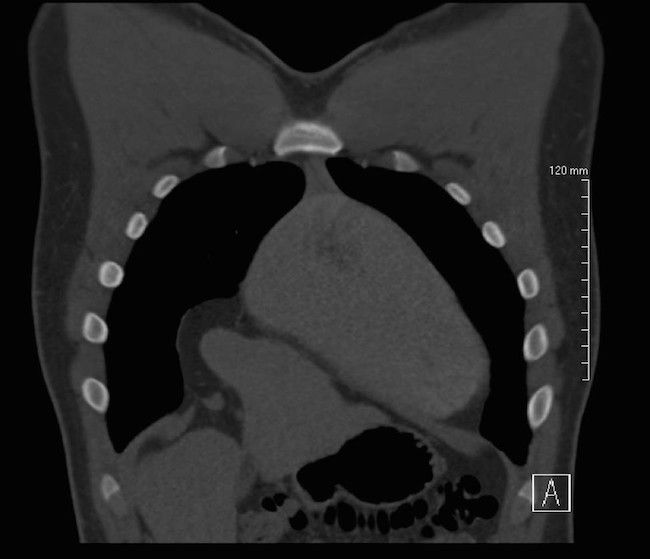

We report a case of a collegiate American style football player presenting to the emergency department with four months of intermittent, non-exertional, midsternal chest pain and pressure. Workup included a computed tomography scan that revealed intrathoracic herniation of the left lobe of the liver through a large Foramen of Morgagni hernia over the right aspect of the heart. Data to guide management is sparse but favors surgical intervention. The patient pursued non-operative management and successfully returned to play to complete a full season of NCAA football as a starting defensive end without complication. This case refutes the common practice of immediate surgical intervention in patients with Morgagni hernias.

A 19 year old previously healthy male, NCAA defensive end, presents with four months of intermittent, non-exertional, midsternal chest pain and pressure. The pain is described as an episodic band like pressure radiating across the epigastrium. At maximum the pain is rated four out of ten and is completely relieved with holding a deep inspiration. There are no other mitigating or exacerbating factors. There are no other associated symptoms. This has never happened previously. Initial workup in the emergency department with chest radiograph revealed a right cardiophrenic angle mass. Electrocardiogram, complete blood count, comprehensive metabolic panel, lipase and troponin were within normal limits. Computed tomography scan revealed intrathoracic herniation of the left lobe of the liver through a large Foramen of Morgagni hernia over the right aspect of the heart. The patient obtained cardiothoracic surgery consultation and opted to forego surgical intervention while symptoms remained mild to moderate. The patient successfully returned to play and completed a full season as an NCAA defensive end without complication. The patient has another year of eligibility and plans to complete his collegiate career without surgery if symptoms remain stable.